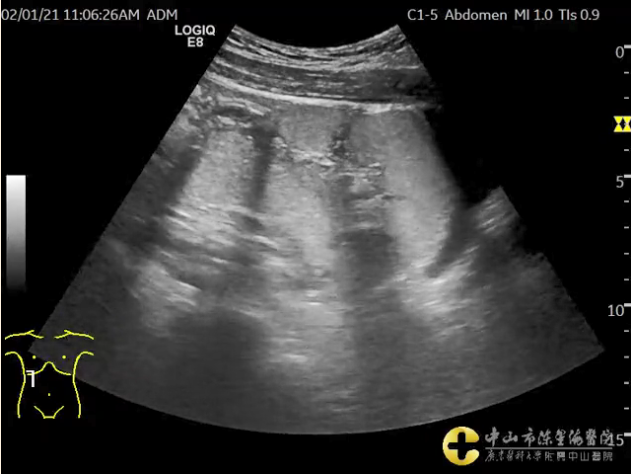

超声显示充盈的结肠及动态充盈的过程